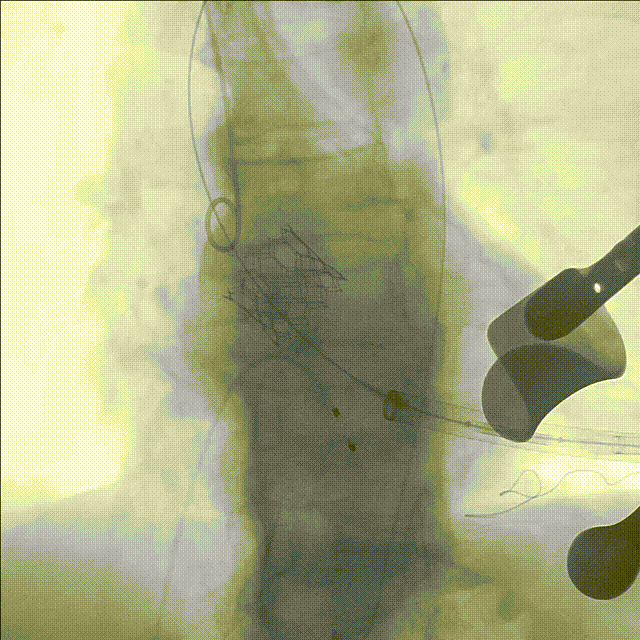

复查造影示瓣膜位置,功能,形态良好,无冠脉堵塞,术中TEE证实主动脉瓣生物瓣位置及功能正常,未见瓣周漏,仅微量反流。

术后造影